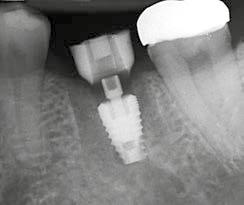

6. kép: Implantátum-ágy preparáció. 7. a–b. képek: Implantátum behelyezés. 8. kép: A behelyezett implantátum. 10. a–b képek: Azonnali ideiglenes korona készítése. 9. kép: Megfelelő primer stabilitás.

10. c–d képek: A kész ideiglenes korona. 11. kép: A 6 hónapos kontroll felvétele.

12. kép: A 6 hónapos intraorális kontrollröntgen felvétele.

A 2020 januárjában elkezdett kezeléssorozat befejezését az év márciusában, hazánkba is begyűrűző Covid-19 pandémia késleltette, így kb. 6 hónap gyógyulás után láttunk hozzá az emergencia profil és a gingivális zenit ideiglenes koronával történő formázásához (11. és 12. kép). A 3 hetente végzett apró alakításokkal sikerült megfelelő ínyprofilt kialakítani, a „rózsaszín esztétika” a páciens számára is megfelelő volt. A bal felső nagymetsző fog meziális kompozit tömés cseréjét követően, individualizált nyitott kanalas lenyomati fejet készítettünk: az akrilát ideiglenes korona profilját átlátszó szilikonnal lemásoltuk, majd a körszimmetrikus gyári lenyomati fej és az ideiglenes korona kontúrja közötti hézagot folyékony kompozittal töltöttük ki (13. kép). Az így készített egyéni lenyomati fejjel vettünk lenyomatot a végleges, kerámialeplezésű cirkónium-dioxid vázas, átmenő csavaros rögzítésű koronához. (A fogtechnikai munkát Nébl Péter fogtechnikusmester készítette.), (14., 15., 16 és 17. képek).